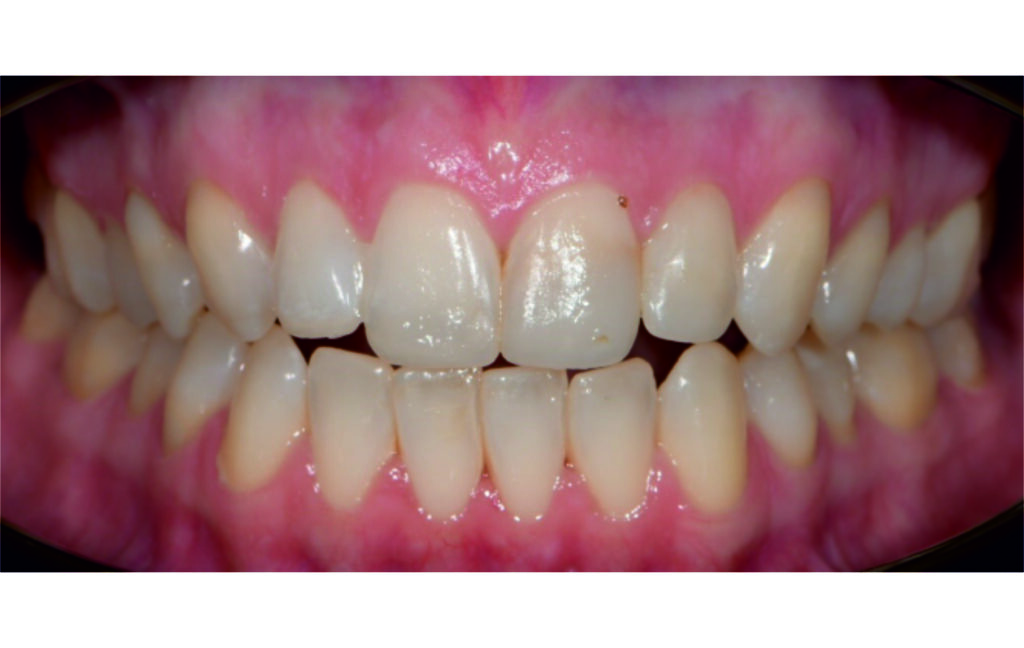

Initial Photos and datas

Angle Class II 2mm on the right, Angle Class II 2mm on the left, light mandibular asymmetry to the right, lower central line 1mm to the right, upper central line 1,5mm to the left, 1mm overjet and overbite. Sagittal asymmetry of upper dental arch. Light crowding upper and lower frontal segments, severe attrition of posterior teeth, night bruxism. Normal sagittal position of both jaws, high angle case, steep mandibular ramus,excessive lower facial height, open bite tendency.